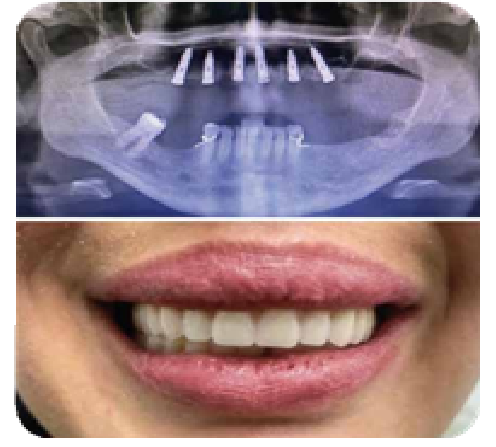

IMPLANTE ALL ON SIX CASO CLÍNICO

Nuestra paciente manifiesta que desea volver hablar, masticar y sonreír con normalidad después de un largo tiempo.

Después de analizar su caso decidi- mos optar por un tratamiento de prótesis sobre implantes all on six, al terminar el proceso la paciente se encontró CONTENTA con el resultado.